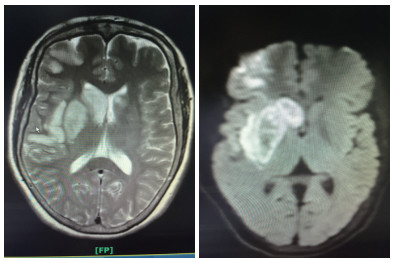

患者女性,55岁,住院号:526777。主诉:左侧肢体乏力1 h余。现病史:缘于入院前1 h余始无明显诱因出现左侧肢体乏力,持物、行走不能,伴有构音含糊,无吞咽困难、饮水呛咳,无意识障碍,无抽搐、二便失禁,无头晕头痛呕吐,无畏冷发热,无咳嗽咳痰,无心悸气喘,无腹痛腹泻,无双下肢水肿。在外未诊治,急诊行头颅CT后送入本科。既往史:无。个人史:无烟酒嗜好。体格检查, 查体:体温: 36.5℃, 脉搏: 72次/min, 呼吸: 20次/min, 血压: 126/76 mmHg。双肺呼吸音清,未闻及干湿性啰音;心率72次/min,律齐,各瓣膜区未闻及杂音;周围血管征阴性;专科查体:神志清楚,构音含糊,对答切题,双眼向右侧凝视,左侧鼻唇沟浅,口角歪向右侧,伸舌偏左,左侧肢体肌力1级,右侧肢体肌力5级,肌张力正常,深、浅感觉正常,膝反射、跟腱反射等腱反射对称活跃,克匿格征、布鲁金斯基征阴性,左侧巴彬斯基征阳性,右侧病理征未引出,共济运动及闭目难立征欠合作。NIHSS评分14分。辅助检查:头颅CT示双侧基底节区腔隙性脑梗死;入院诊断:①脑梗死②糖尿病?治疗;患者处于溶栓时间窗,入院后完善相关检查无明显溶栓禁忌证,经家属同意,予阿替普酶溶栓(患者体质量55 kg,予阿替普酶50 mg溶栓,其中5 mg静推,余剂量予1 h泵入),并予“吡拉西坦8 g静滴,1次/d,依达拉奉30 mg静滴,2次/d”等治疗,第2天患者左侧肢体乏力、构音含糊较前改善,查体:构音稍含糊,双眼无凝视,左上肢肌力1+级,左下肢肌力3级,溶栓后第1天复查颅脑CT平扫:右侧基底节区及额颞叶大面积脑梗死,并右侧基底节区出血性脑梗死可能性大(阅片考虑可疑高密度灶非出血灶,考虑正常脑组织),予加用波立维75 mg,1次/d、立普妥20 mg每晚睡前1次、尤瑞克林0.15 PNA静滴,1次/d。溶栓后第2天颅脑MR平扫(1.5T):①双侧基底节区、双额叶多发梗死灶、腔隙灶。②脑干腔隙灶?③部分空泡蝶鞍。患者住院共11 d,出院时患者左侧肢体乏力、构音含糊较前改善,查体:构音稍含糊,双眼球活动正常,左侧鼻唇沟略浅,口角略歪向右侧,伸舌略偏左,左上肢肌力2+级,左下肢肌力4+级,NIHSS评分5分。